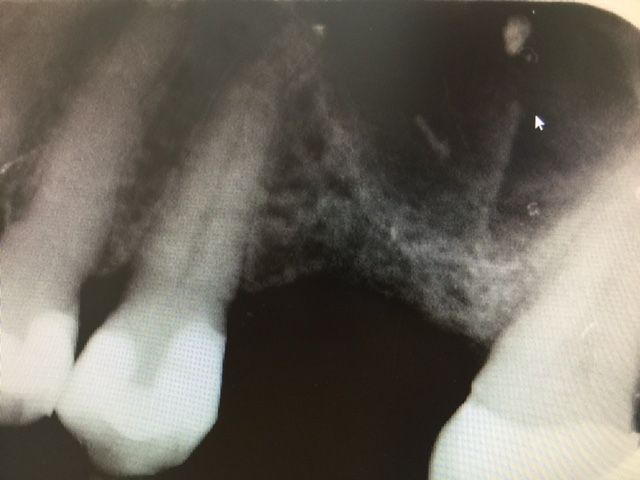

CAS N°1